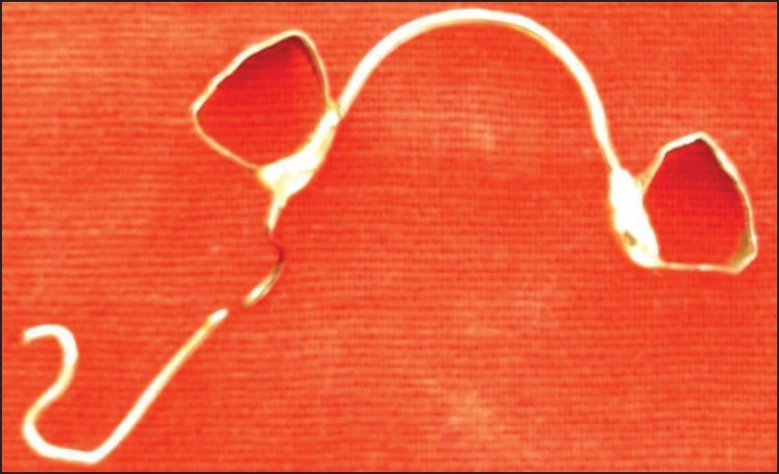

A standard 0.036 stainless steel arch wire was adapted on the lingual surface and soldered to the band. An U – bend was incorporated near the left mandibular primary second region with a distal extension consisting of a hook shape at the terminal end of wire [Figure 6] The appliance was cemented with distal hook engaging the occlusal button placed on the surgically exposed permanent mandibular left first molar and U - bend was activated. The patient was recalled after 2 weeks and the amount of tooth movement was assessed by observing the gaps between the occlusal button and primary second molar. It was determined that more movement was necessary and so the activation loop were again gently opened. After 3 weeks, considerable movement was appreciated clinicall [Figure 7].The appliance was left in place for another 3 weeks to minimize the chances of relapse. Fifty six days after cementation appliance was removed. Occlusal button was removed and the teeth were sealed with pit and fissure sealant as a preventive measure to reduce the risk of caries. In 4 months, the permanent first molar developed in a proper position [Figure 8].

Figure 6.

Appliance design